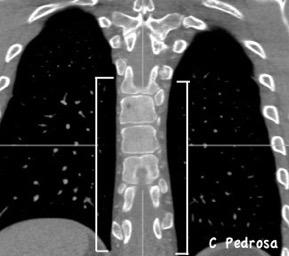

Líneas paraespinales formando un “paréntesis” por encima del diafragma. El signo señala el origen “intratorácico” de la lesión.

Conrad A et al. Pott’s disease associated with large and multiple abscesses in a 30-year-old migrant from Chad. BMJ Case Rep 2018

(lesiones toracoabdominales) La divergencia de las líneas paraespinales apunta a lesión toracoabdominal, que desde el tórax desciende y penetra en el abdomen.

Signo del “iceberg” positivo en Tb vertebral